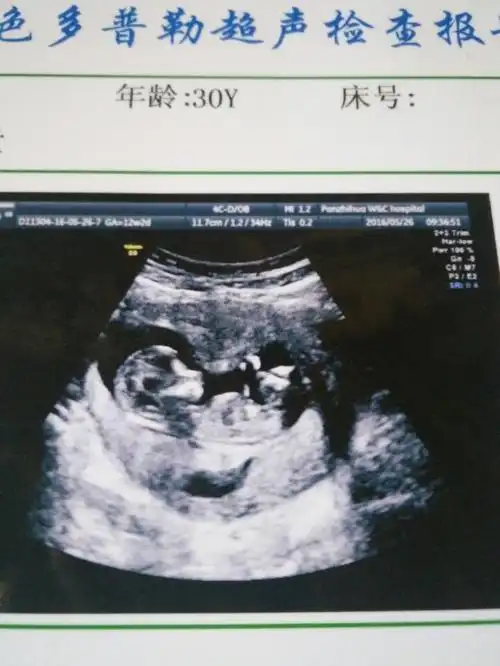

1cm,体重约16.4g,如图所示7070两胎儿的发育情况

12周nt能看出男女嘛

可以看出男孩女孩吗?12周

12周nt顺利通过!感恩!